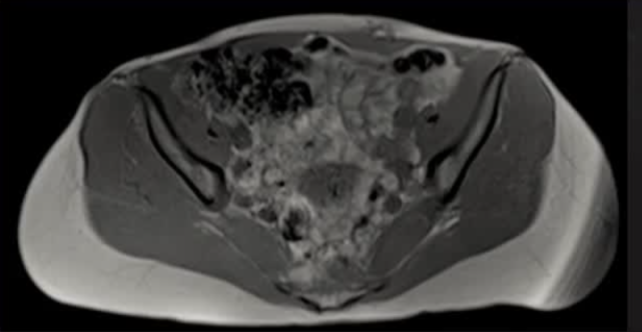

病灶位置:16个疼痛性目标病灶位于脐部(7/16,43.8%)、膈肌(4/16,25.0%)、腹股沟管(3/16,18.8%)和子宫肌肉层(即腺肌症,2/16,12.4%)。

影像引导方式:超声和横断面成像(CT或MRI)结合是最常用的影像引导方式(10/16,62.5%)。

保护措施:几乎所有干预都需要辅助保护措施,其中水分离术(13/16,81.3%)和水分离术与温盐水填充手套的皮肤保护结合(9/16,56.3%)是最常见的保护措施。

本文通过回顾性研究,展示了经皮影像引导冷冻消融治疗不常见解剖位置疼痛性子宫内膜异位症病灶的有效性和安全性。研究结果显示,大多数患者在接受冷冻消融后实现了显著的疼痛缓解,且并发症发生率较低。这些发现表明,冷冻消融是一种有前景的治疗方法,尤其适用于传统手术难以到达的病灶位置。核心观点是,该治疗方法不仅能够有效缓解患者的疼痛,而且具有较高的安全性和可行性。